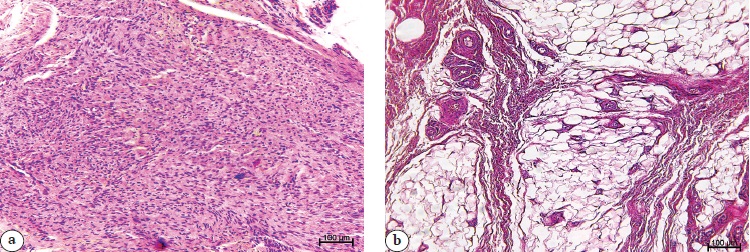

Обнаружены выраженные отличия в строении гиперпластической соединительной ткани и васкуляризации жировой ткани у пациентов сравниваемых групп (рис. 1 и 2).

Рисунок 1. Парафиновые срезы операционного материала пациента из группы 1: a — гиперпластическая соединительная ткань с повышенным содержанием сосудов микроциркуляторного русла, высокой клеточной плотностью, вихреобразным (или палисадообразным) расположением клеток; b — в гиперваскуляризованной жировой дольке гиподермы выражены периваскулярная клеточная инфильтрация и экстравазация форменных элементов крови. Окраска гематоксилином и эозином. Увеличение ×100

Figure 1. Paraffin sections of the surgical material from a Group 1 patient: a — hyperplastic connective tissue with an increased content of microcirculatory vessels, high cell density, vortex-like (or palisade-like) arrangement of cells; b — in the hypervascularized fat lobule of the hypodermis, perivascular cellular infiltration and extravasation of blood cells are expressed. Hematoxylin and eosin staining. Magnification ×100

Рисунок 2. Парафиновые срезы операционного материала пациента из группы 2: a — гиперпластическая соединительная ткань с редко встречающимися сосудами и высокой клеточной плотностью; b — в жировой ткани преобладают сосуды с фиброзноизмененными утолщенными стенками. Окраска гематоксилином и эозином. Увеличение ×100

Figure 2. Paraffin sections of the surgical material from a Group 2 patient: a — hyperplastic connective tissue with sparse vessels and high cellular density; b — vessels with fibrously changed thickened walls predominate in adipose tissue. Hematoxylin and eosin staining. Magnification ×100

В группе 1 выявлена бо́льшая процентная доля патологически измененных сосудов преимущественно за счет сосудов с инфильтрированными стенками (р = 0,0001), в то время как в группе 2 больше доля кровеносных сосудов с фиброзно-измененными стенками (табл. 2).